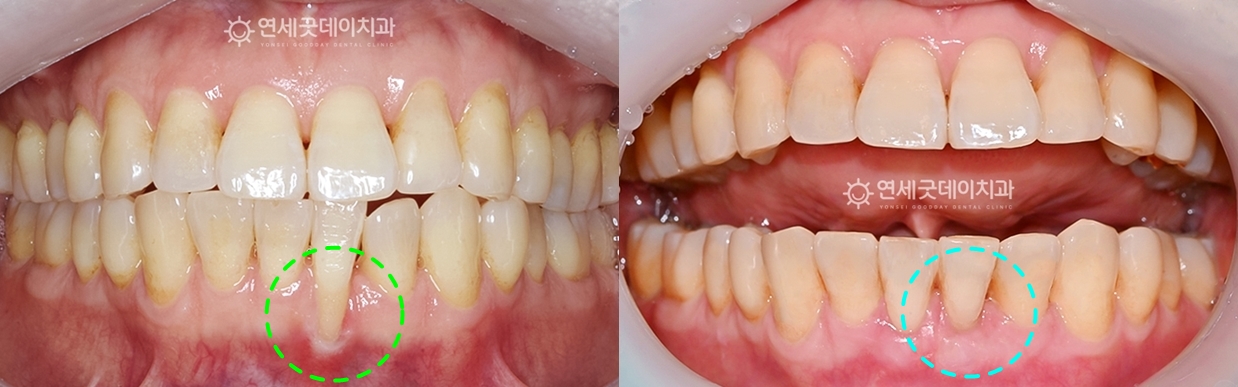

▲ 치료 전 정면 (촬영시기 : 2024년 12월)

육안으로도 아래 앞니의 잇몸이 많이 내려간 게 관찰됩니다.

▲ 치주교정 치료전후 비교 (촬영시기 : 2024년 12월 / 2025년 10월)

약 9개월 간의 아랫니부분교정과 핀홀수술로